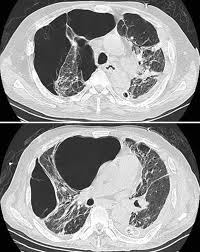

Development Of Bullous Lung Disease In A Patient With Severe Covid 19 Pneumonitis Bmj Case Reports